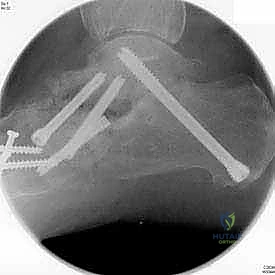

بعد التأكد من الوضعية المثالية للعظام، يتم تثبيتها بقوة باستخدام مسامير معدنية مجوفة من التيتانيوم (Cannulated Screws) أو شرائح معدنية خاصة. يتم إدخال المسامير تحت توجيه الأشعة السينية المباشرة (Fluoroscopy) داخل غرفة العمليات لضمان الدقة المتناهية. هذه المسامير تضغط العظام معاً وتمنع أي حركة حتى يحدث الالتئام التام.